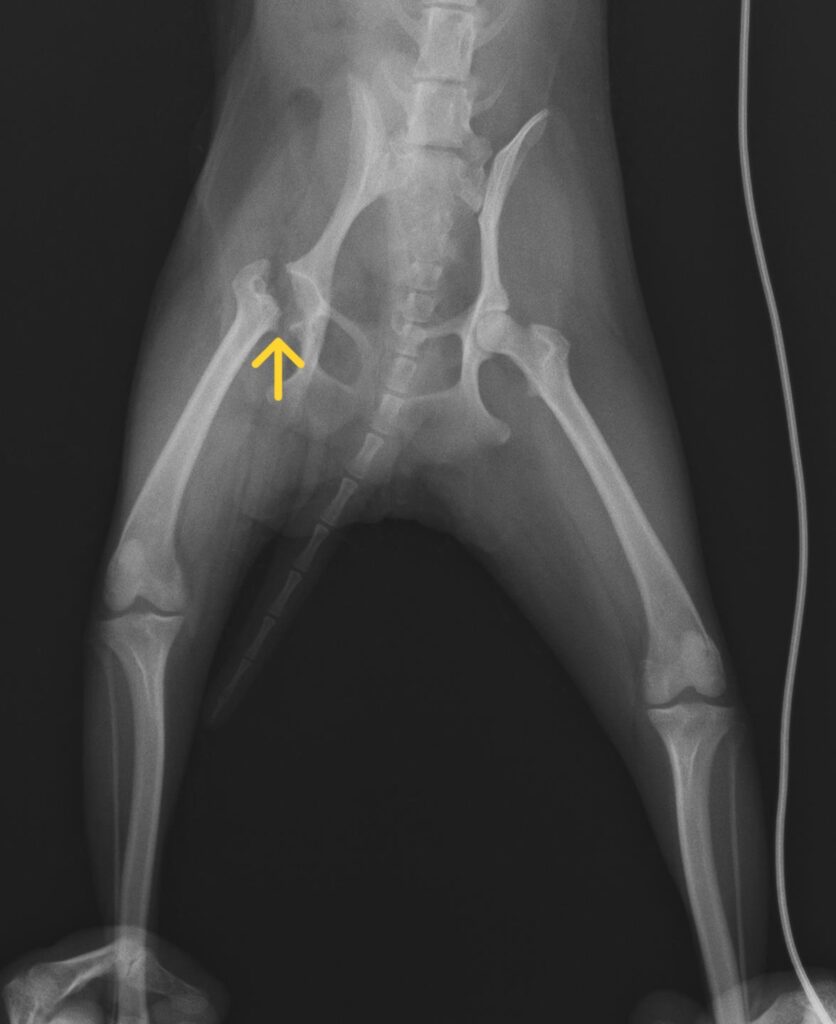

写真中央 大腿骨頭切除後レントゲン所見 矢印:骨頭切除部